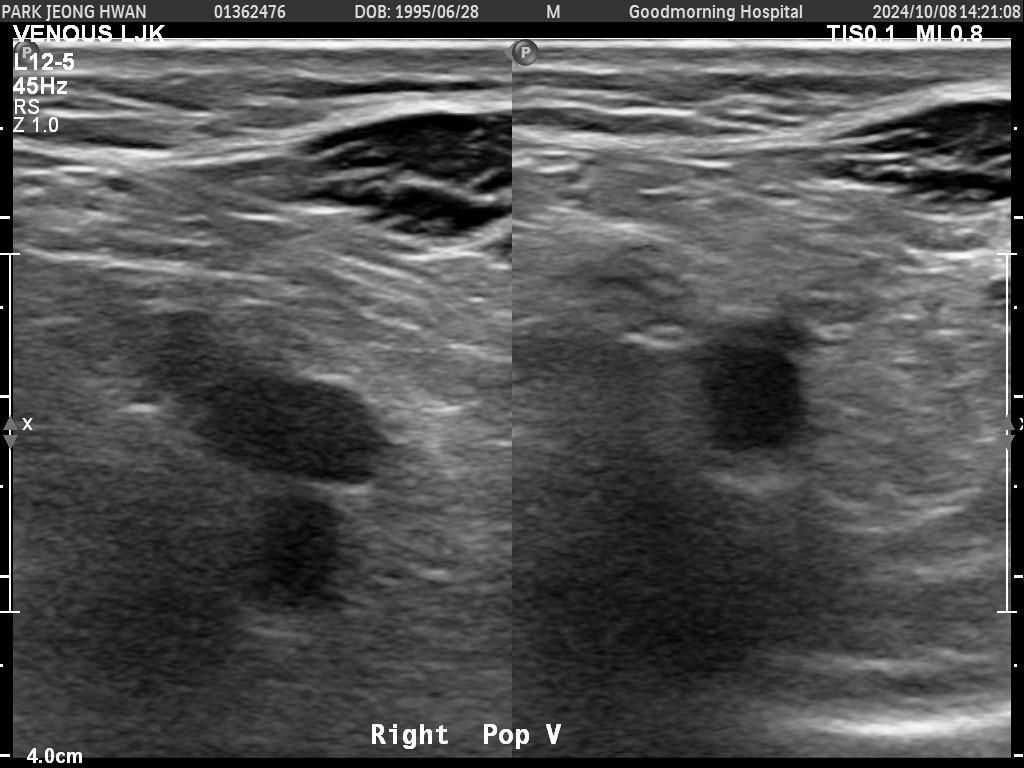

오른쪽 다리만 찍은 거구요. 종아리에서 사타구니까지 부분별로 찍었습니다.......................

• 1번 째 사진

• 2번 째 사진

• 3번 째 사진

• 4번 째 사진

• 5번 째 사진

• 6번 째 사진

• 7번 째 사진